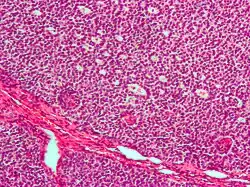

Granulosazelltumor

Granulosazelltumoren sind Tumoren des Ovars mit niedrigmaligner Potenz. Sie werden zu den mesenchymalen und hormonbildenden Ovarialtumoren gerechnet.